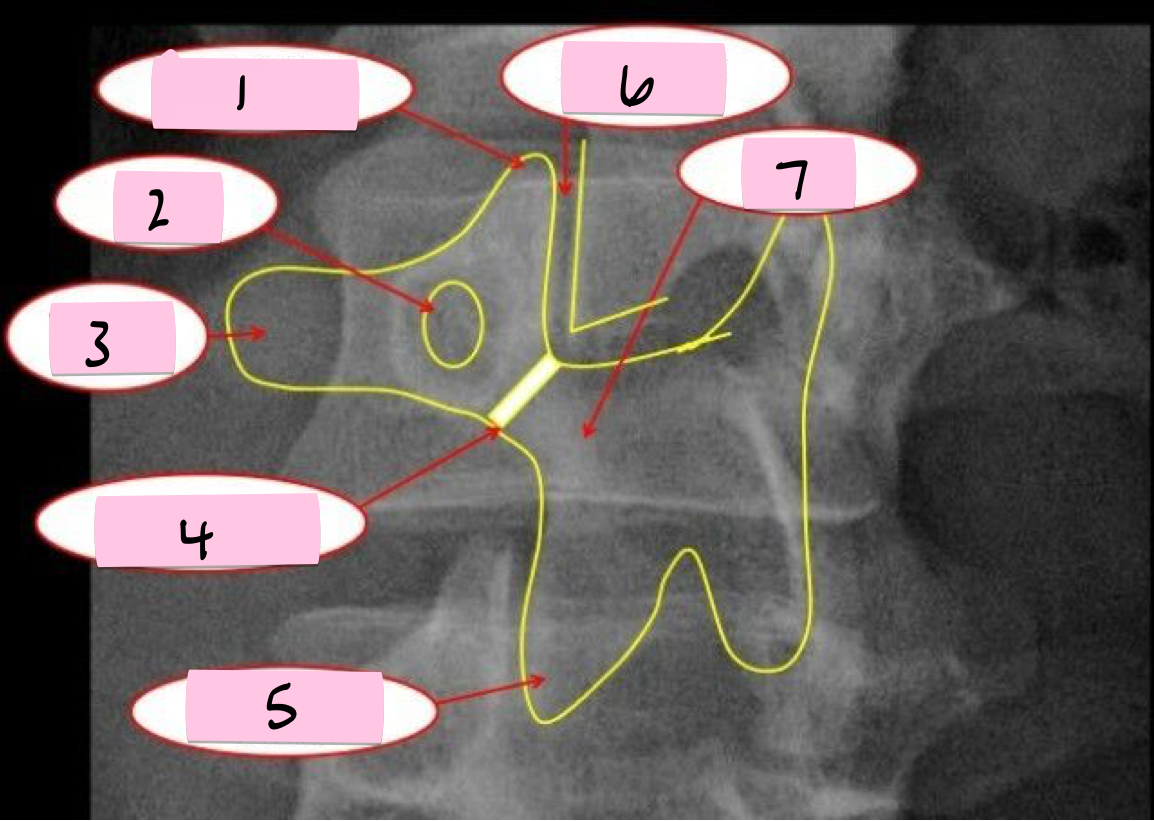

What is 1 pointing to?

Transverse process

What is 2 pointing to?

Intervertebral disk

What is 3 pointing to?

Ala of sacrum

What is 4 pointing to?

Sacrum

What is 5 pointing to?

12th Rib

What is 6 pointing to?

Pedicle

What is 7 pointing to?

Spinous process

What is 8 pointing to?

Psoas muscle

What is 9 pointing to?

Lumbar body (L4)

What is 10 pointing to?

Sacroiliac joint